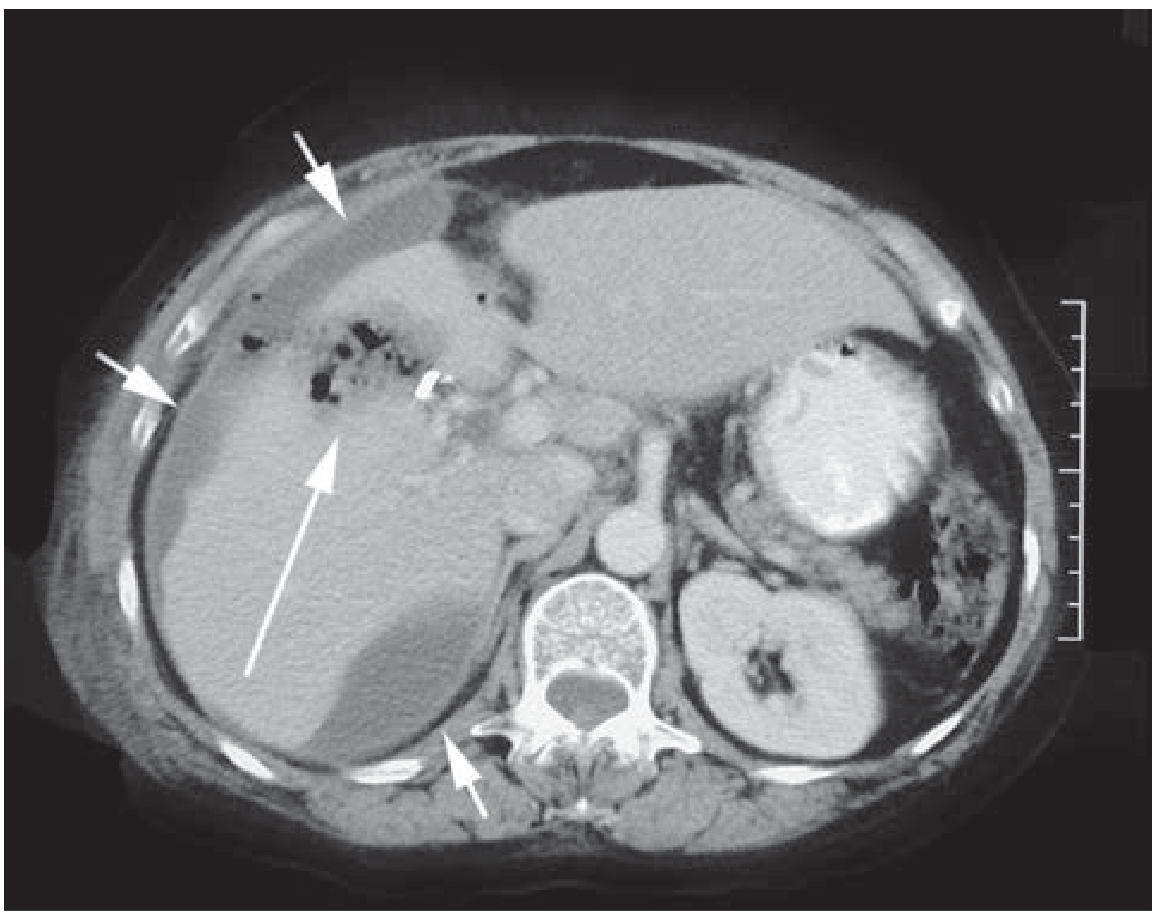

CT Scan — Bile Leak After Cholecystectomy

(Schwartz's Principles of Surgery, 11e)

CT scan showing intraperitoneal bile collections (short arrows) and air/bile in the gallbladder bed (long arrow) after cholecystectomy

Figure A — CT abdomen: Short arrows indicate intraperitoneal fluid collections (biloma); the long arrow points to air and bile in the gallbladder bed, along with a surgical clip. This is the classic post-cholecystectomy bile leak appearance.